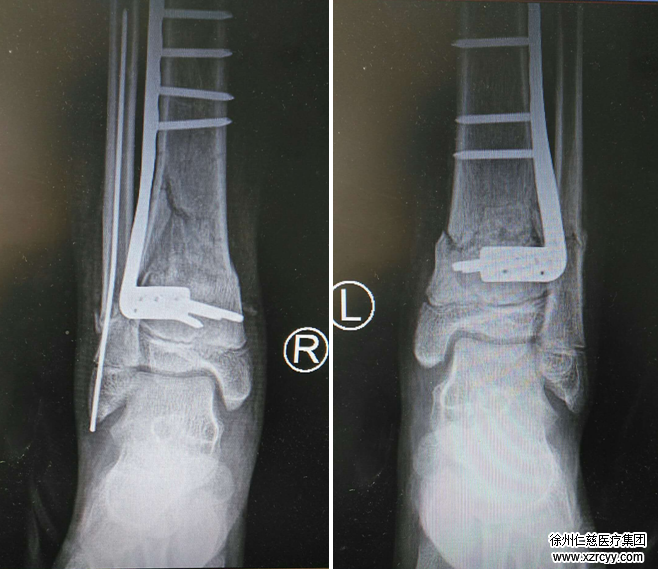

摔伤4个小时后,李加蛟被送到betway在线登陆急诊科。正值足踝科曹广超主任当班,当即给孩子做了检查,结果为双脚胫腓骨下端粉碎性骨折,累及踝关节,双胫腓骨下端骨骺损伤,右桡骨小头骨折,两个脚踝肿得很厉害。

经过5天的消肿后,小李骨折的双踝出现了手术指征。一系列术前准备后,曹广超、赵亮手术团队为小李实施了左胫腓骨骨折切开复位内固定+右胫腓骨骨折切开复位内固定术。

术中,先进行左胫骨骨折切开复位内固定,在左小腿前外侧切15cm的切口,见患者胫骨骨折断端错位明显,累及踝关节,并伴有胫骨骨骺损伤,又在小腿后内侧切5cm的口子,复位骨折端,置入“L”型锁定接骨板,定住骨折块;右胫腓骨骨折同样处理,双侧踝关节辅以石膏夹板外固定。手术共进行了5个小时,获得成功。

手术后,小李被推入足踝病区休养,用药康复。2周后,伤势良好的他办理了出院手续。出院前,曹主任叮嘱他按医嘱来定期复查片子,半年后就可以来取下钢板。